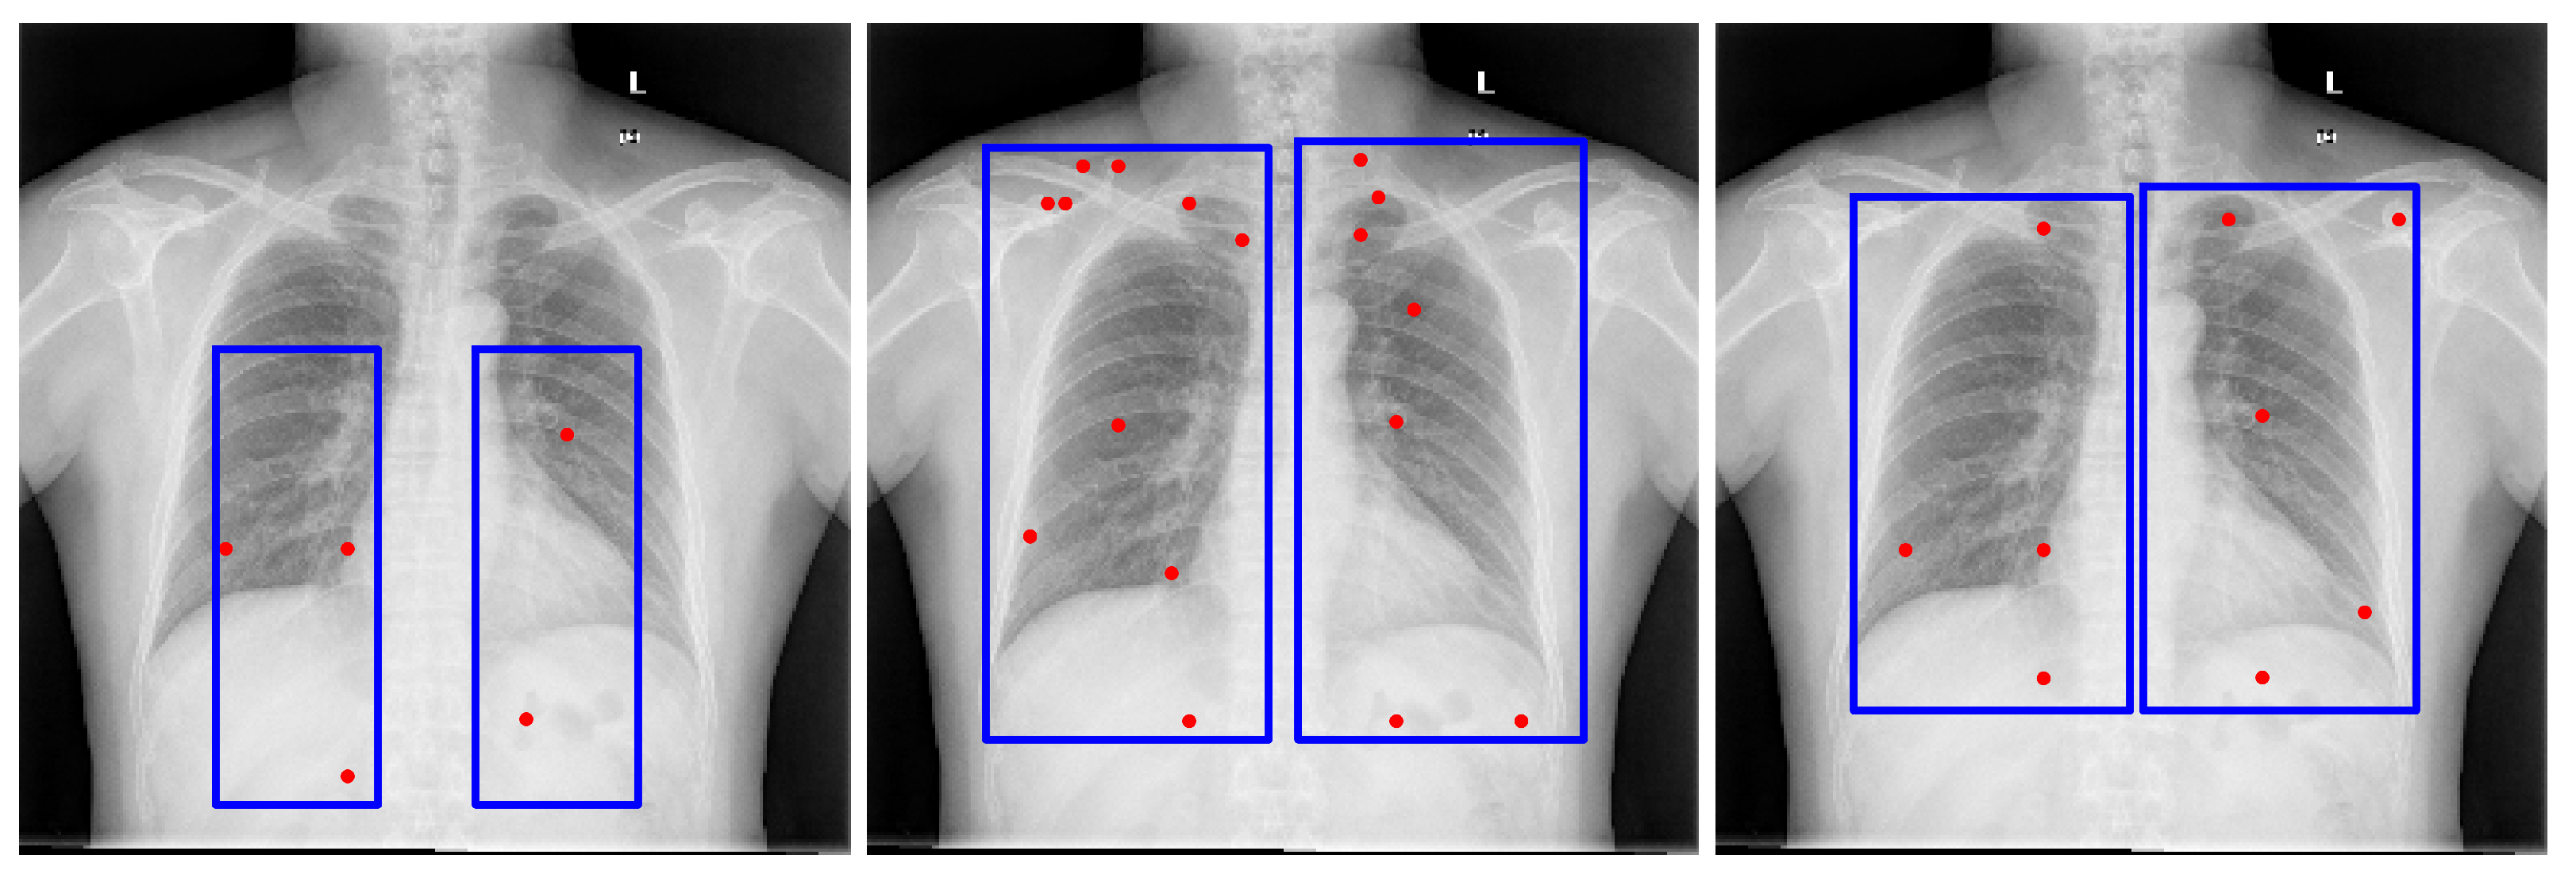

Figure 3. Bounding box estimations by Gemini Pro 2.5 across different datasets. Blue rectangles and red dots indicate the prompts provided to SAM for generating segmentation candidates.

GPT-4o [13] demonstrated performance comparable to Gemini Pro 2.5 [9] in our internal evaluations; however, Gemini Pro 2.5, available from Google, was chosen for downstream experiments due to its consistent accuracy, stable API access, and available research funding for sustained API usage. It also outperformed LLaMA-based models, as shown in Figure 2. Model outputs were returned in JSON format and integrated directly into our segmentation pipeline. While the bounding box estimations generated by Gemini across multiple datasets were not sufficiently precise to serve as final segmentations, they consistently localized the region of interest. Despite occasional boundary inaccuracies, these estimations provided reliable spatial priors that effectively guided the SAM model towards more accurate segmentations, as illustrated in Figure 3.

The proposed pipeline begins with prompt-engineered Gemini Pro to estimate precise bounding boxes for the target anatomical structure. From these bounding boxes, SAM is used to generate segmentation candidates by point prompting within the predicted region, while an additional candidate is generated directly from the initial Gemini-derived bounding box. Candidate selection is performed using CLIP, which computes similarity scores against a prototype embedding derived from multiple representative segmentation masks. The whole process is depicted in Figure 1.